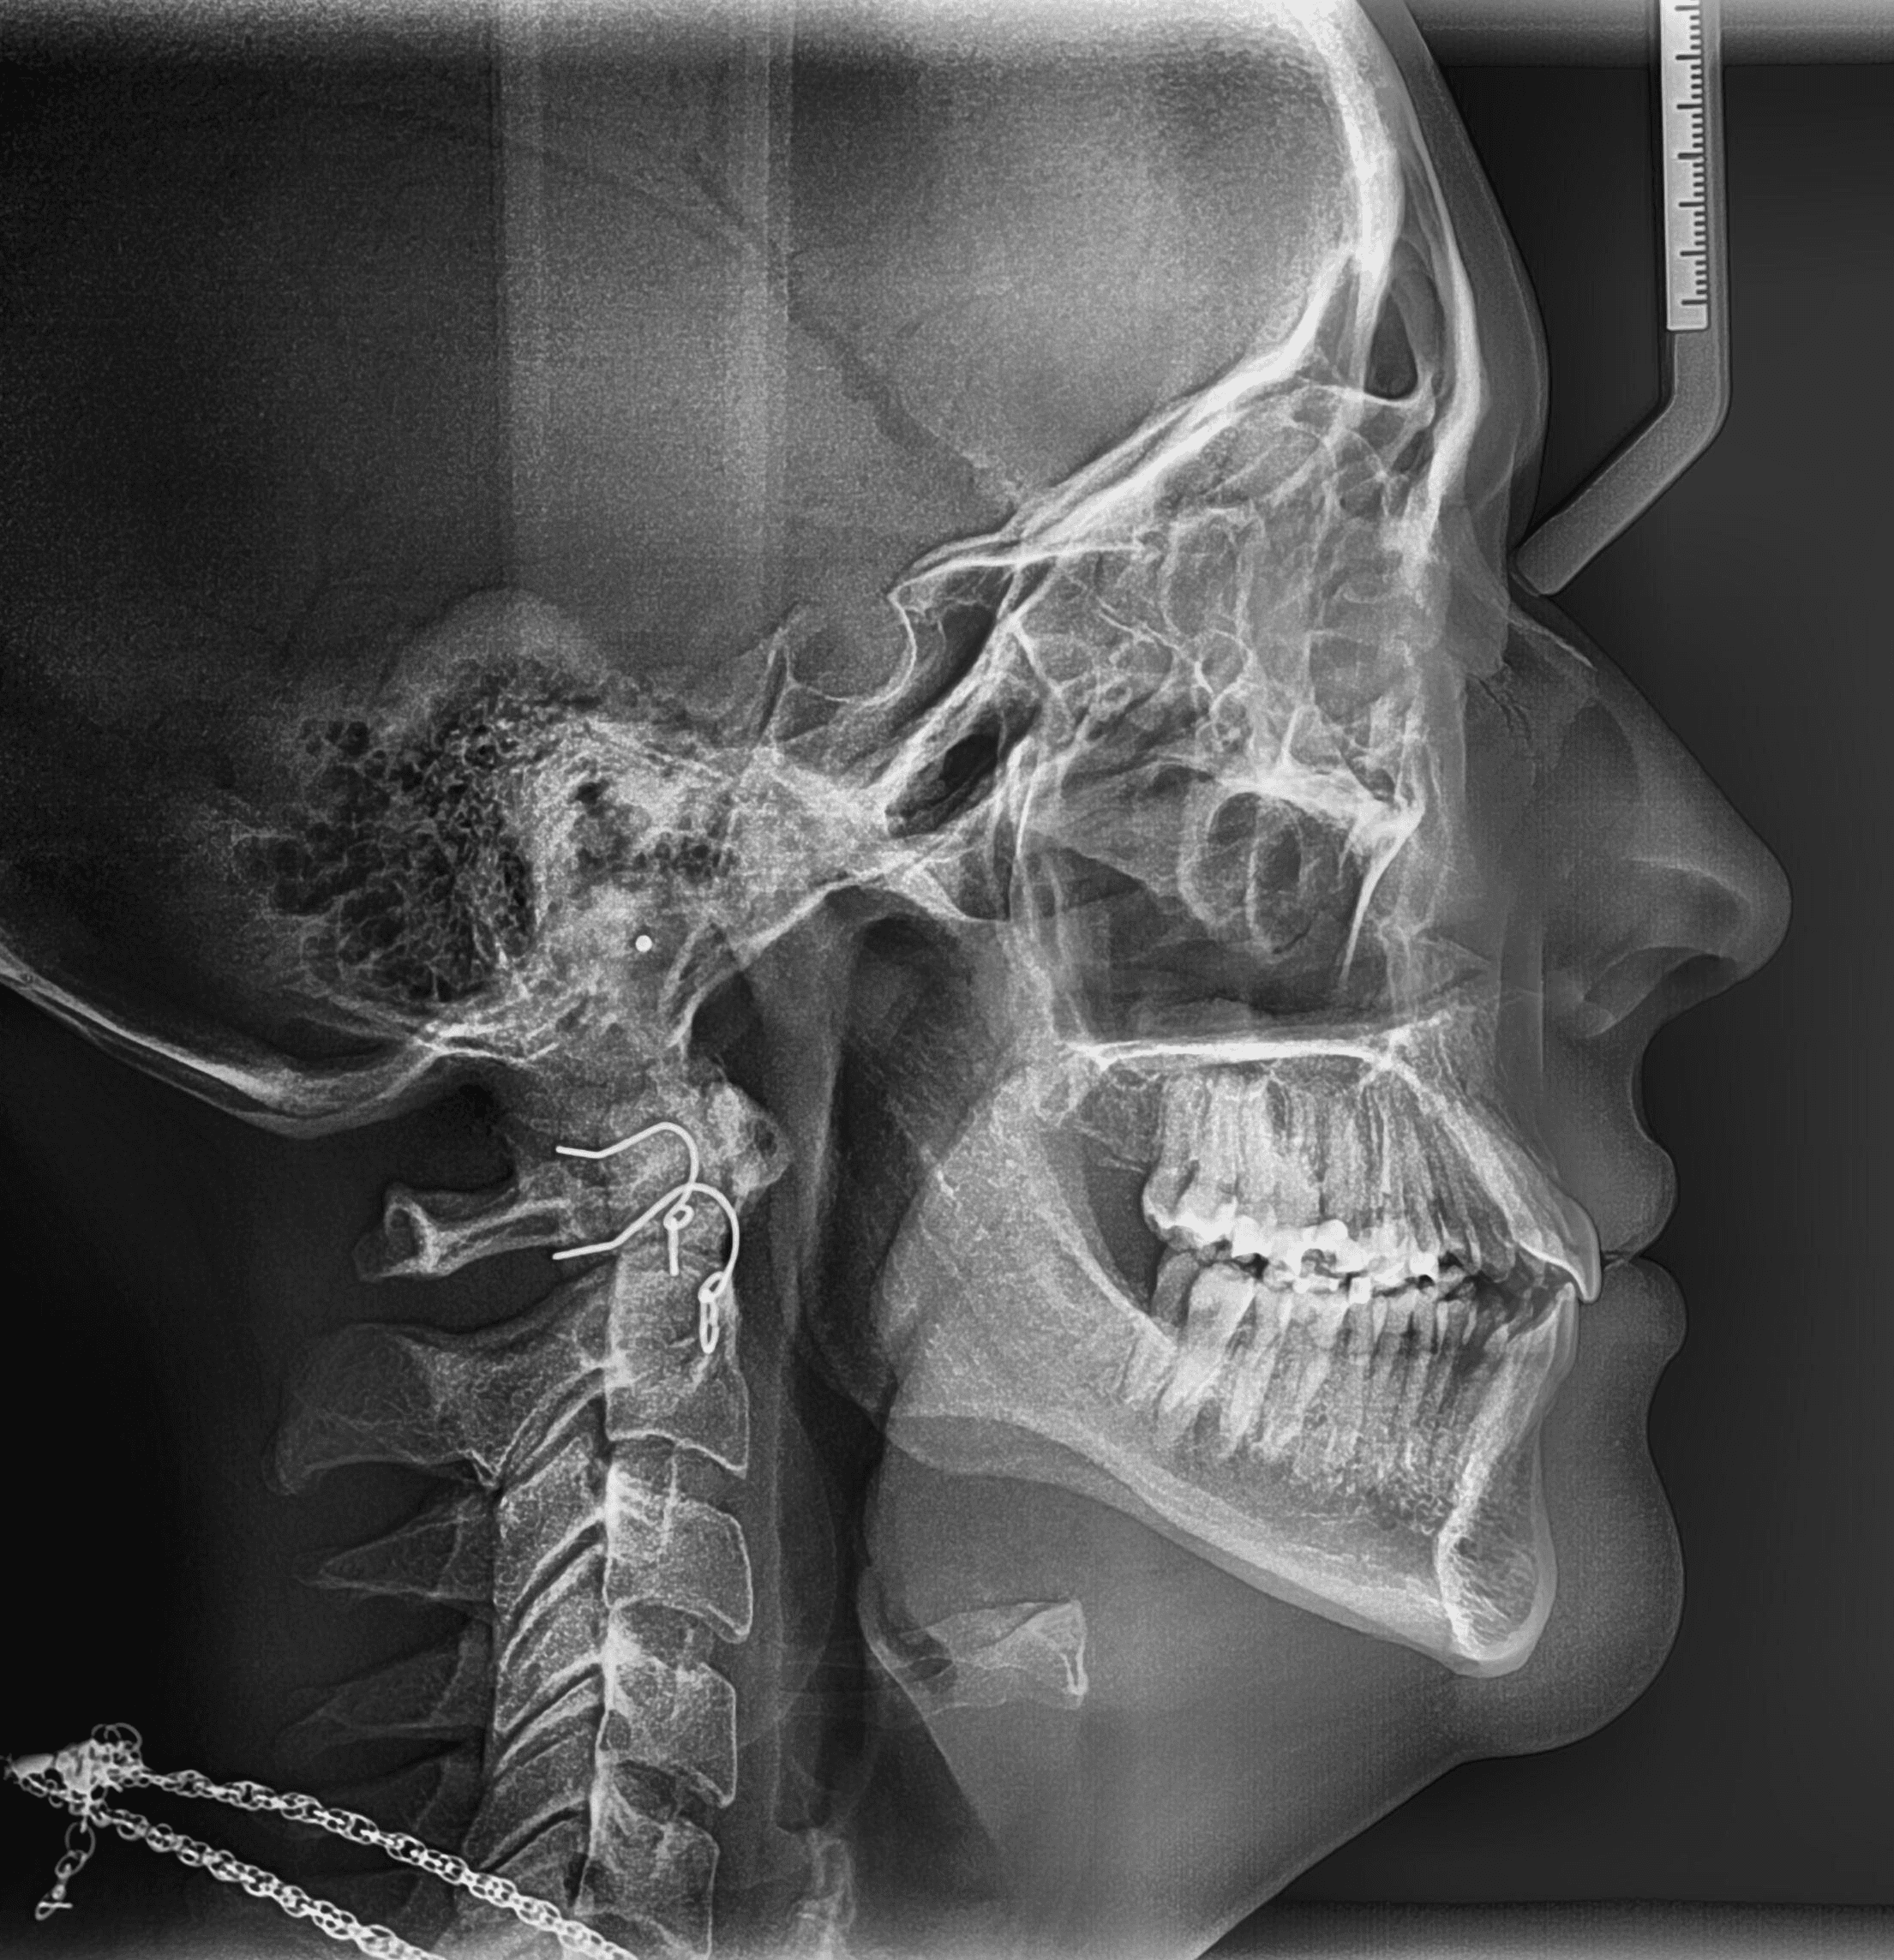

X-RAYS